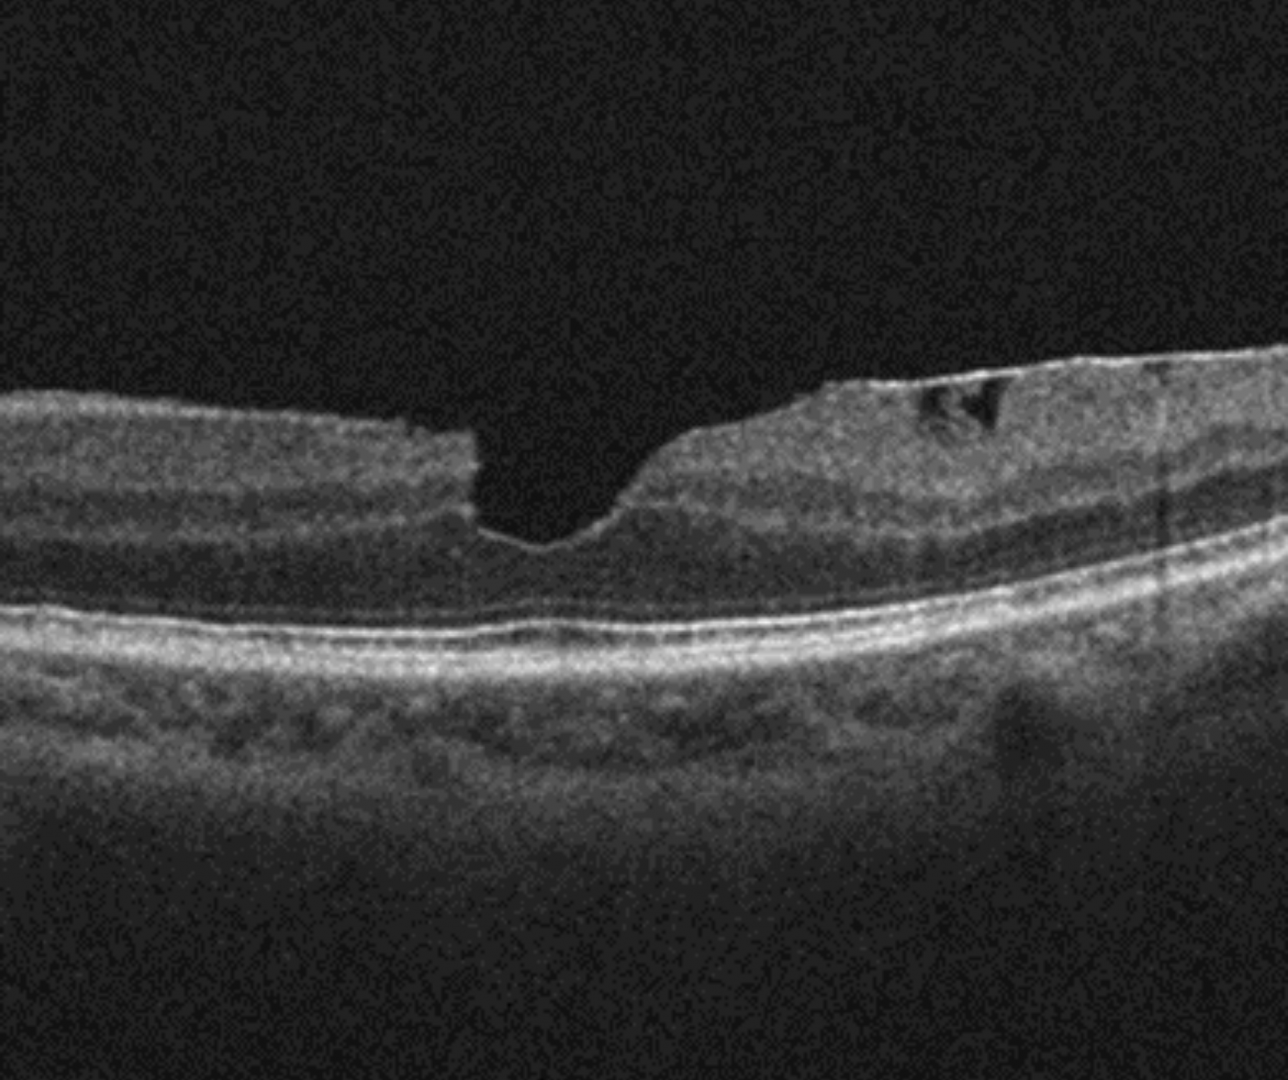

On OCT, a macular pseudohole is defined by three characteristics: the presence of a verticalized or steepened foveal profile, retinal thickening and an ERM sparing the foveal centre.

Spectralis OCT macula line scan (right eye)